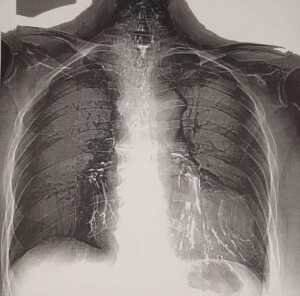

Остатки бария сульфата в бронхах у пациентки с пищеводно-бронхиальными свищами